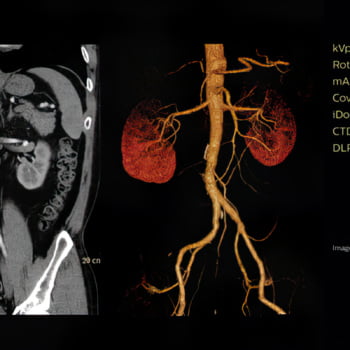

Veja mais detalhes em uma grande variedade de pacientes

A exclusiva tecnologia MAR reduz os efeitos de objetos metálicos na formação das imagens, permitindo a visualização da anatomia circundante. Nossa alta resolução espacial revela detalhes sutis para um alto nível de análise quantitativa, maximizando a detectabilidade de pequenos objetos.